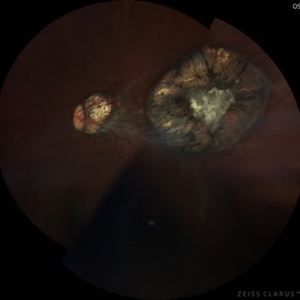

Serpiginous-Choroiditis-Like

Fundus photograph of a 26-year-old woman with a serpiginous-choroiditis-like presentation secundary to a tuberculosis activation disease, started with visual acuity and systemic syntomps

Photographer: Andrés Santiago Pérez-Giraldez, MD. Asociación para evitar la Ceguera en Mexico I.A.P. Mexico

Condition/keywords: ocular tuberculosis, serpiginous choroiditis, tuberculosis